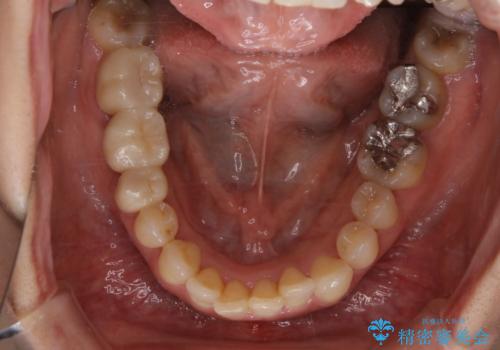

- 前歯のがたつきと反対咬合を主訴に来院されました。

インビザライン・クリンチェック(歯のシミュレーション)を行い、

インビザラインライトで治せる範囲であることを確認し治療を開始することになりました。

今回はクリンチェックを作成したのちに、枚数が少なくても可能であることが判明したためインビザラインライトでの治療を行いました。

最初はインビザラインモデレートパッケージの予定で契約をされていたので、金額も10万円以上安くなり仕上がりも満足頂きました。